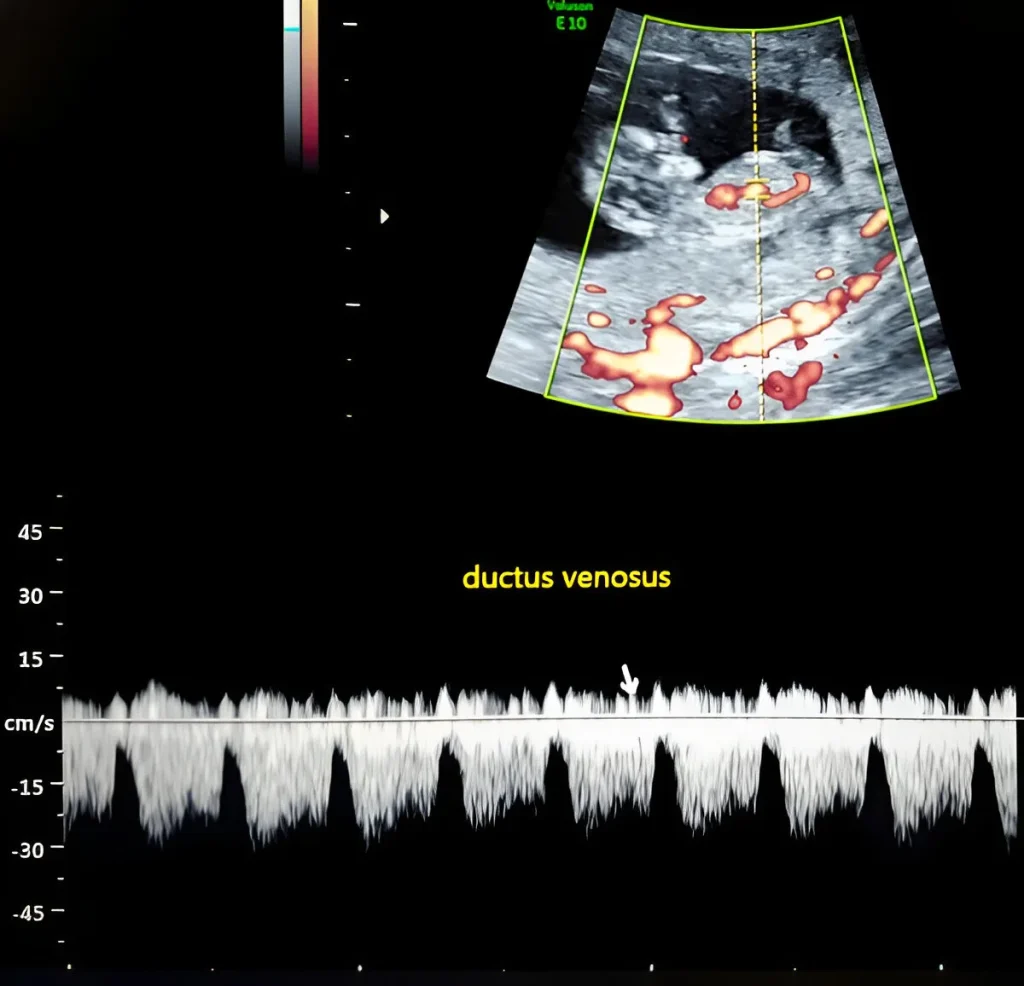

Ductus Venosus Doppler – Fetal Cardiac Health and Chromosomal Risk Scan

At Henotic Diagnostics, our Ductus Venosus Doppler scan ensures accurate fetal cardiac health and chromosomal risk assessment. Indeed, you can expect compassionate care with advanced precision from our experienced female radiologists. In fact, we follow ISUOG protocols and NABL-accredited standards. Additionally, we specialize in 3D Uterine Artery Doppler, 3D Umbilical Artery Doppler, 3D MCA Doppler, and 3D Ductus Venosus Doppler in Kharghar & Navi Mumbai. Similarly, we provide Uterine Artery Doppler, Umbilical Artery Doppler, MCA Doppler, Placental Doppler, and 3D Power Doppler Angiography in Kharghar & Navi Mumbai for monitoring fetal oxygen flow and maternal blood supply assessment. Additionally, we offer affordable, expert Obstetrics (OBS) Doppler in Kharghar & Navi Mumbai. Book your Best Obstetrics (OBS) Doppler Near You or the Best Obstetrics (OBS) Doppler in Kharghar & Navi Mumbai today.